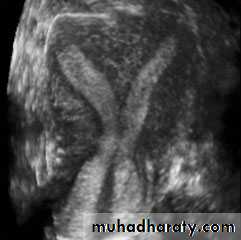

• Uterus

• Reconstructed coronal view of the uterus demonstrating cornuas (arrow) and cervix, with a normal uterine contour